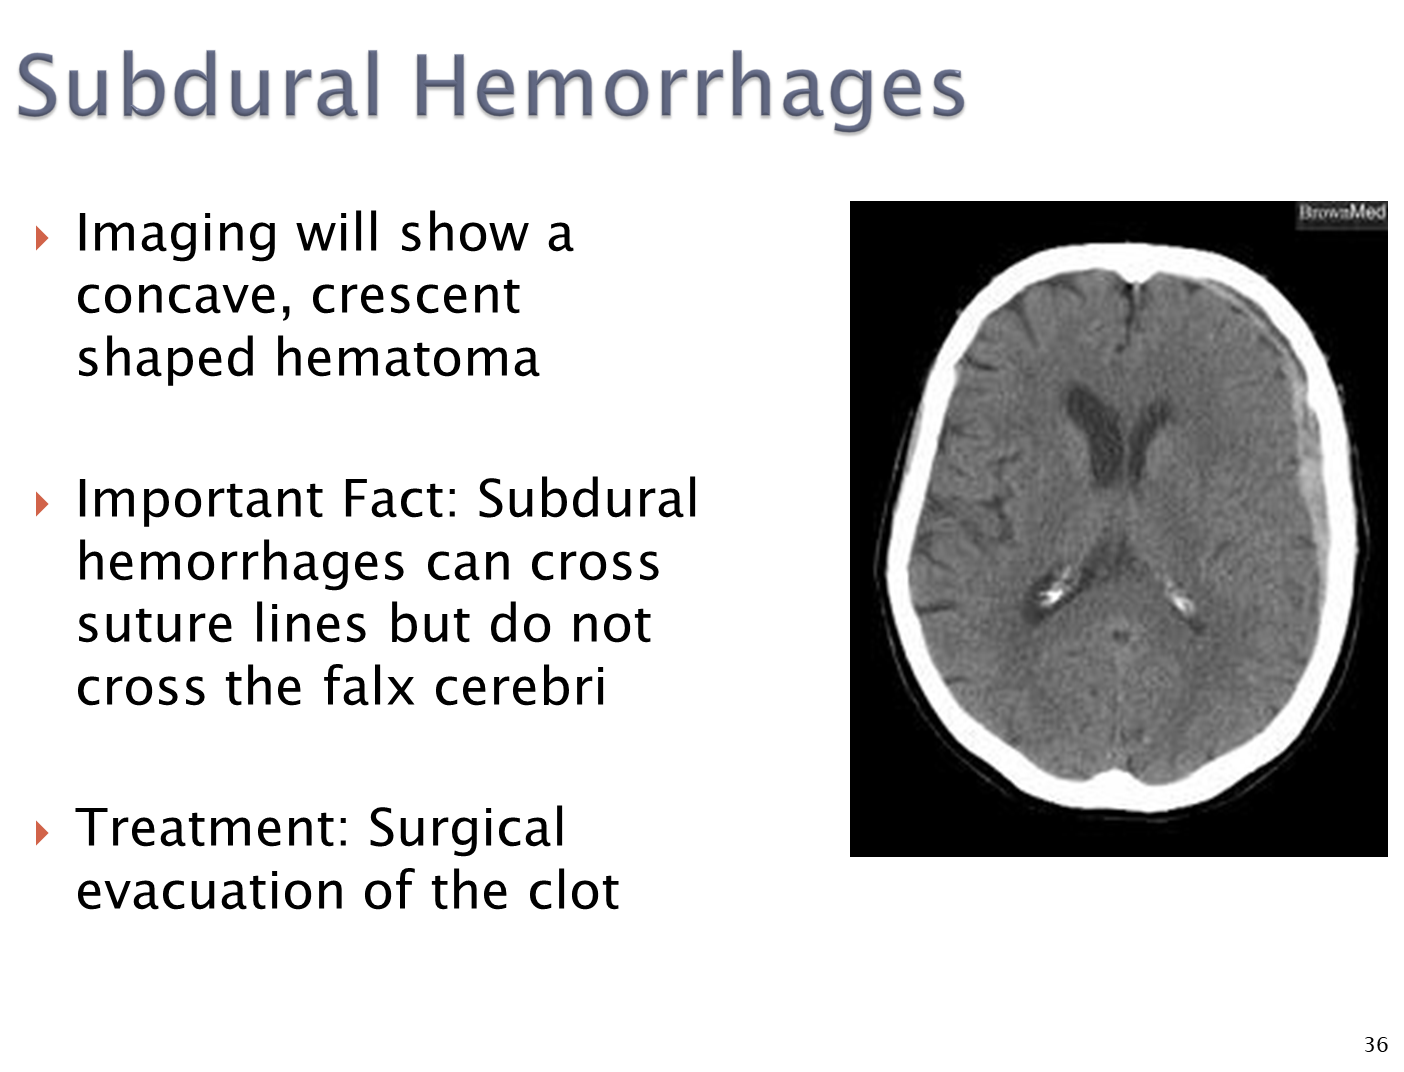

How does a subdural hemorrhage present on a CT scan and how is it treated?

CT - concave crescent shaped hematoma

→ subdural hemorrhages can cross suture lines but will not cross the falx cerebri

→ treated with surgical removal of the clot